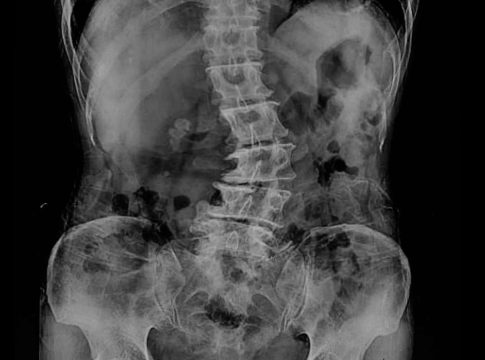

La radiología digital dinámica (Dynamic Digital Radiography -DDR, por sus siglas en inglés) es una innovadora tecnología de rayos X que permite obtener series de imágenes digitales en la que se aprecia la anatomía en movimiento. «El equipo, emite 15 pulsos por segundo durante un tiempo de exposición de 15 segundos, lo que ofrece una imagen dinámica de la anatomía del paciente de forma muy rápida», explica el Dr. Vicente Martínez de Vega, jefe del Servicio de Diagnóstico por la Imagen del Hospital Universitario Quirónsalud Madrid, que dispone del primer equipo portátil en Europa de estas características. Este equipamiento de la empresa Konica Minolta ofrece a los radiólogos la posibilidad de capturar y analizar el movimiento fisiológico de una estructura corporal con una dosis muy inferior a un estudio por fluoroscopia.

«La radiología digital dinámica tiene utilidad en los estudios ortopédicos en los que se aprecia una imagen radiográfica del movimiento de las articulaciones como la muñeca, el hombro o la rodilla. También tiene gran utilidad para estudiar la columna en flexión y extensión. Nos ofrece una visión muy completa del movimiento de la articulación», explica el Dr. Martínez de Vega, que también cree que esta nueva tecnología tiene otro punto fuerte en los estudios de función pulmonar: «Puede tomar imágenes de dos o tres respiraciones completas del paciente y mostrarnos una imagen en movimiento en el que se visualiza con claridad cómo se llenan y vacían los pulmones y el movimiento del diafragma. Se aprecia si existen adherencias pleurales o si hay zonas que no ventilan correctamente. A la información visual del cineloop (imágenes en secuencia), se pueden añadir mapas de ventilación y del movimiento realizados gracias a softwares avanzados específicos de la estación de trabajo, que analizan las diferentes densidades del pulmón y ofrecen al radiólogo datos cuantificables de función pulmonar». Según el Dr. Martínez de Vega, esta información es muy útil en las Unidades de Cuidados Intensivos en los que ayudará a valorar más adecuadamente la evolución de los pacientes desde el punto de vista cardiopulmonar. Otra gran ventaja de este equipo es que es portátil, lo que permite realizar los estudios a pie de cama de los pacientes sin necesidad de desplazarlos.

«La radiación que recibe un paciente que se somete a una radiografía digital dinámica es similar a una placa postero-anterior y lateral de rayos X convencional, pero aporta mucha más información», detalla el Dr. Martínez de Vega, que afirma que la radiología digital dinámica ofrece una información nueva que no habíamos visto hasta ahora: «Hemos pasado de obtener información morfológica a información funcional y cuantificada».